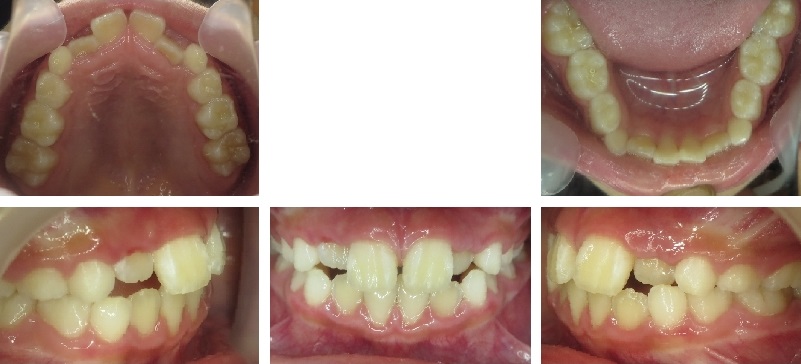

Before crowding

After crowding